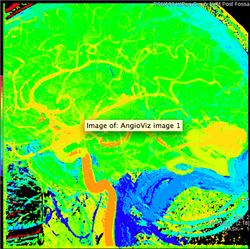

AngioViz uses peak time and density with color as time, and peak density as brightness to show contrast flow timing and magnitud

In one image, AngioViz can show peak pixel density value over an image series. This can indicate relative contrast density and d

AngioViz can show the time that each pixel reaches peak density on a color coded time scale. This helps indicate contrast flow t

A New Visualization of Vascular Flow

AngioViz provides a new visualization of the vascular flow seen in DSA imaging, utilizing a technique called parametric imaging. AngioViz looks at each pixel in the image series and determines two things — the peak value of opacification caused by the contrast, and the time it takes for that pixel to reach peak opacification. These two parameters can be displayed as separate images or combined into a single color-coded image that represents parameters of vascular flow. This enables doctors to perceive parameters of flow quickly to support decision-making. In addition, AngioViz allows easy comparison of parametric images from different DSA acquisitions, such as pre- and post-treatment images. This can help physicians understand the impact on flow dynamics of various interventional treatments.